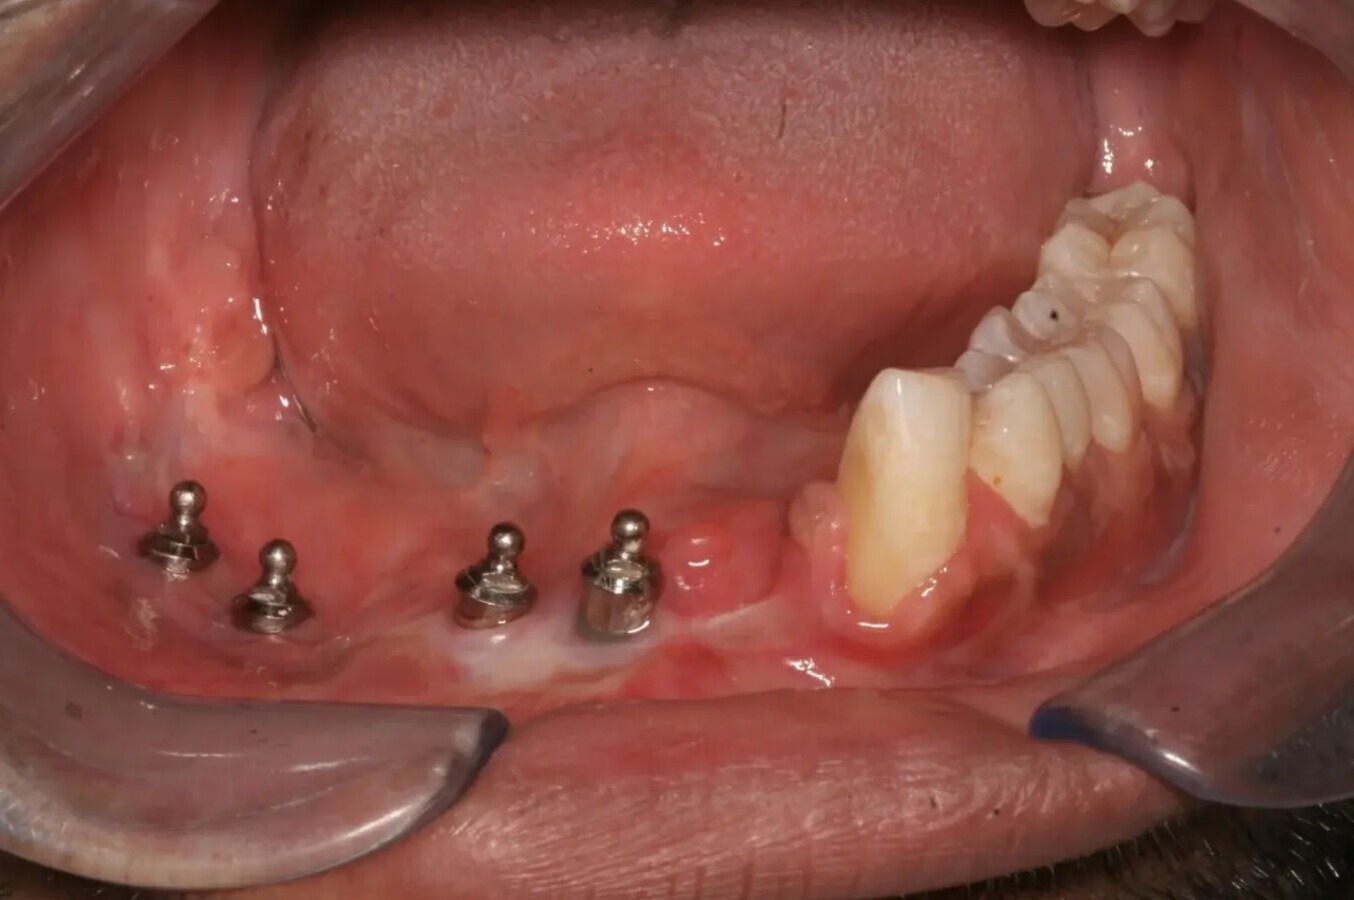

Fig. 2: OPG di un paziente di 9 anni dopo la riabilitazione dentale supportata da impianto. Si osservano i livelli ossei marginali stabili.

Fig. 3: quadro clinico intraorale dello stesso paziente. Notare la presenza di mucosa cheratinizzata sana attorno agli impianti nella mandibola ricostruita dal lembo libero dal perone.